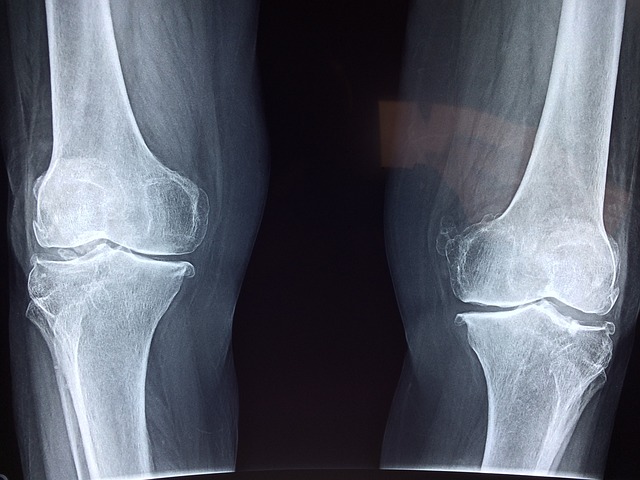

퇴행성 관절염은 전 세계 수백만명 사람들에게 영향을 미치며

관절을 완충시키고 연골의 퇴행을 특징으로 하는 진행성 관절 질환입니다.

퇴행성 관절염 증상

골관절염이라고도 하는 퇴행성 관절염의 증상을 이해하는 것은 조기 발견과 적절한 관리에 매우 중요합니다.